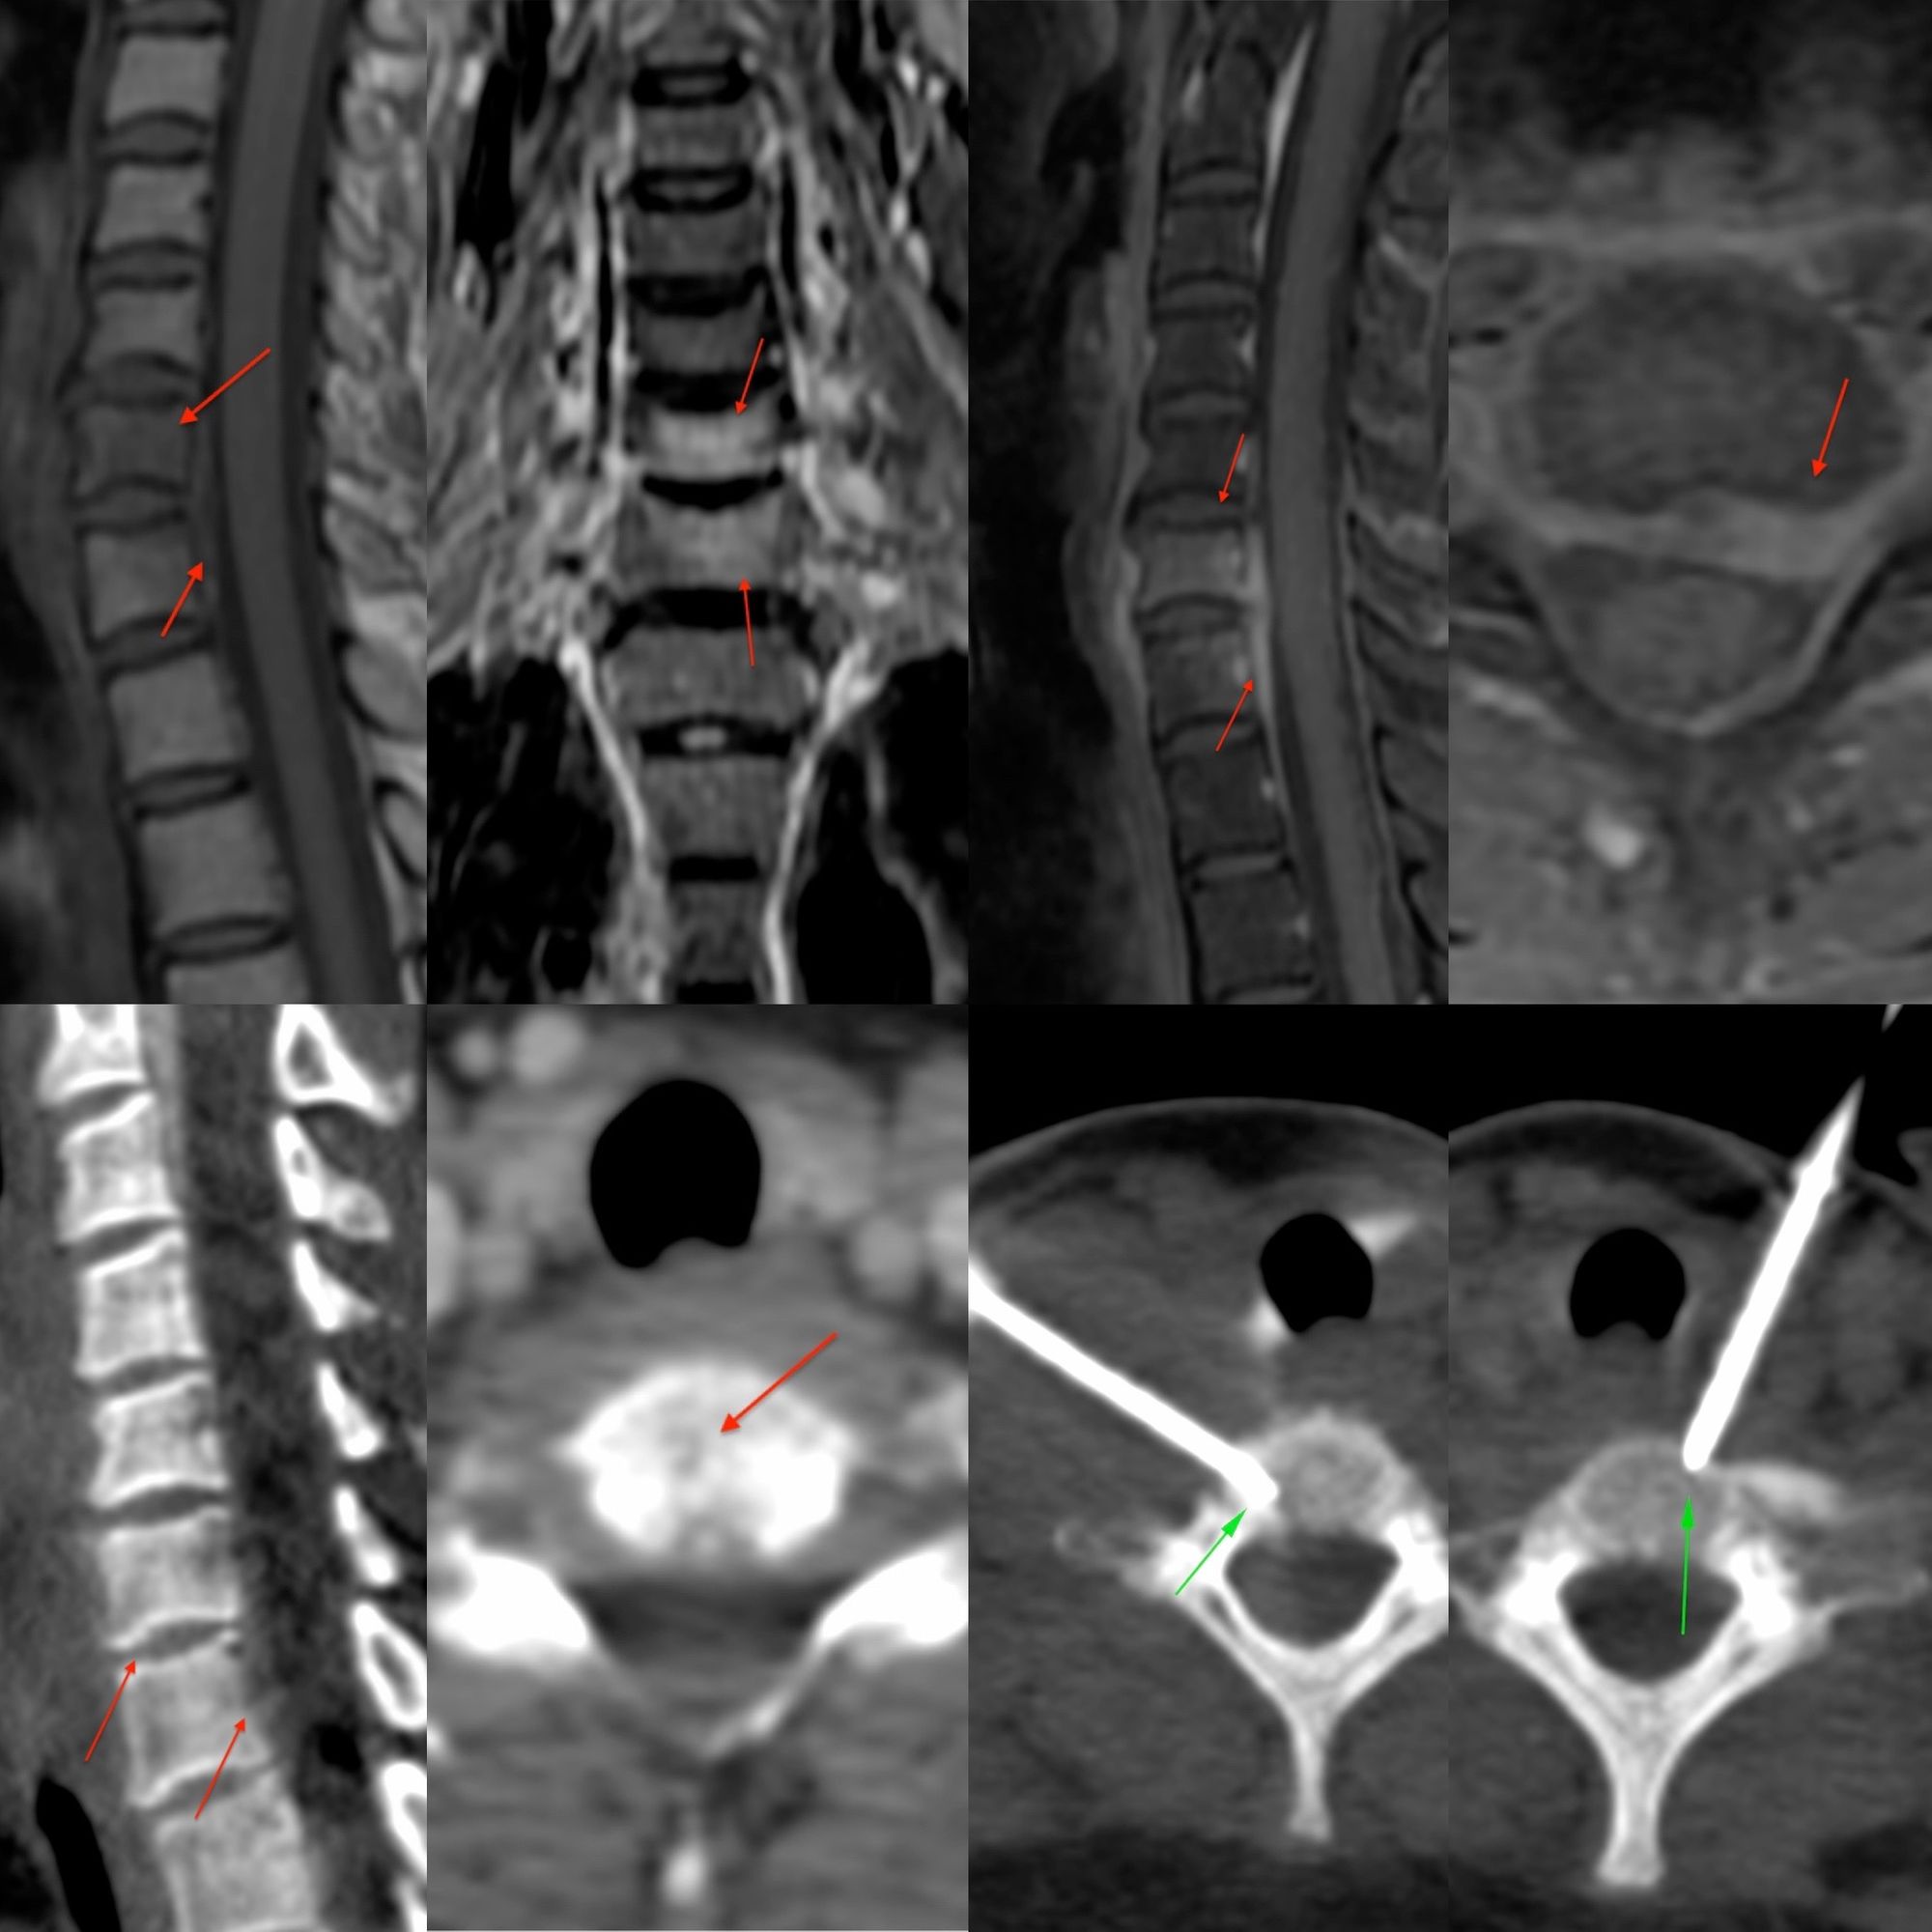

Case 54: C3 Vertebral Body Lesion Biopsy Using a Far Posterolateral Approach

Bhavin Jankharia - 13 August 2021